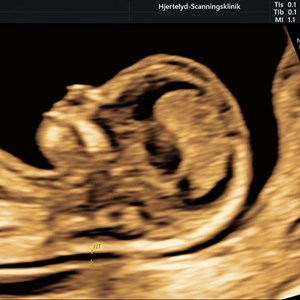

Hjertelyd - scanningsklinik for gravide

Tidlig scanning på foster uge 11+6 Når mor og far ser 1. gang hvor meget baby kan OG kan...